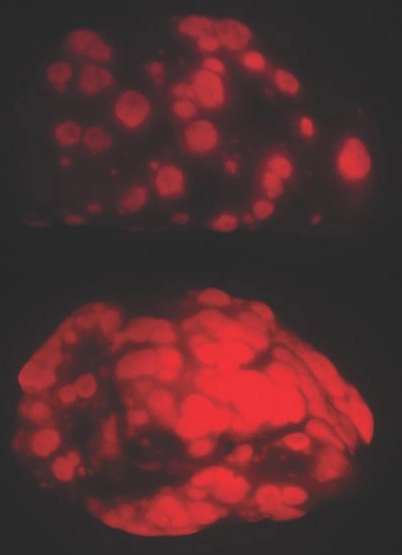

“The improvement is really quite dramatic,” Blau said. “The old mice are about 15% to 20% stronger after one month of treatment, and their muscle fibers look like young muscle. Considering that humans lose about 10% of muscle strength per decade after about age 50, this is quite remarkable.”

Conversely, increasing the expression of the protein in young mice caused their muscles to atrophy and weaken.